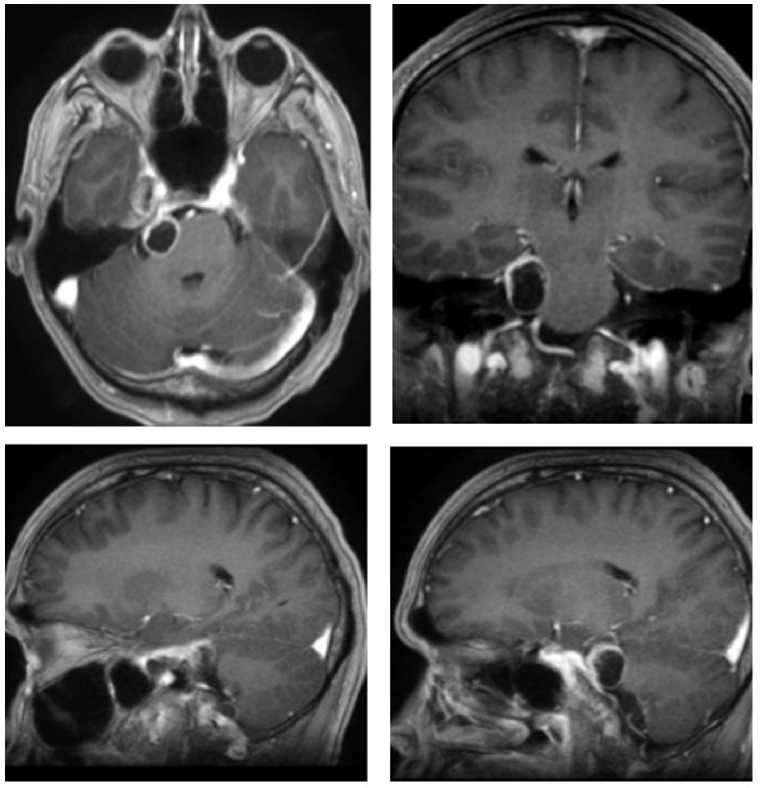

В НМИЦ нейрохирургии им. ак. Н.Н. Бурденко обратился пациент О., 33 лет. Развитие заболевания протекало в течение года в виде онемения в правой половине лица и болью в области внутреннего угла глаза. По данным МРТ, выявлена внемозговая опухоль средней и задней черепных ямок справа, накапливающая контрастное вещество, размеры узла в СЧЯ 1,2 × 1,25 × 1,4 см, в ЗЧЯ — 2,16 × 1,9 × 1,56 см (рис. 4). Объем опухоли в СЧЯ — 2,37 см3, в ЗЧЯ — 3,85 см3. При объективном обследовании перед операцией выявлены нарушения функции тройничного нерва справа в виде снижения роговичного рефлекса, а также горизонтальный нистагм.

Рис. 4. МРТ пациента О. до операции. Внемозговая опухоль СЧЯ и ЗЧЯ, накапливающая контрастное вещество

Fig. 4. MRI of patient O. before surgery. Extracerebral tumor of MCF and PCF with contrast enhancement

Учитывая наличие в ЗЧЯ опухоли большего объема с кистозным компонентом и компрессию ствола мозга, было принято решение о проведении комбинированного лечения. Первым этапом стало микрохирургическое удаление, вторым — лучевая терапия на опухоли в СЧЯ.

Через 6 мес. после операции пациенту проведено лучевое лечение на аппарате Кибер-нож в режиме радиохирургии. Разовая доза — 13,52 Гр, объем облученной опухоли составил 3,46 см3. На МРТ перед лучевой терапии визуализирован фрагмент невриномы тройничного узла в СЧЯ справа размерами 1,56 × 1,59 × 1,35 см, объем опухоли 2,46 см3 (рис. 6). В клинической картине на момент облучения сохранялась гипестезия и снижение роговичного рефлекса, однако через 3 мес. присоединились парестезии в лице и слабость жевательной и височной мышц на стороне операции.

Через 1 г. после лучевой терапии в клинической картине пациент отмечает частичное восстановление чувствительности на лице, а также появление недостаточности VIII черепного нерва справа. Контрольная МРТ продемонстрировала уменьшение опухоли, размеры — 1 × 1,88 × 0,74 см, объем — 0,73 см3 (рис. 6).

Рис. 6. МРТ пациента О.: А — перед лучевой терапией: невринома в СЧЯ, опухоль в ЗЧЯ удалена тотально; Б — через 6 мес. после лучевой терапии: небольшой остаток опухоли в СЧЯ; В — через 1 г. после лучевой терапии: небольшой остаток опухоли в СЧЯ

Fig. 6. MRI of patient O.: A — before radiation therapy: neuroma in MCF, tumor in PCF completely removed; Б — 6 months after radiation therapy: small tumor remnant in MCF; В — 1 year after radiation therapy: small tumor remnant in MCF